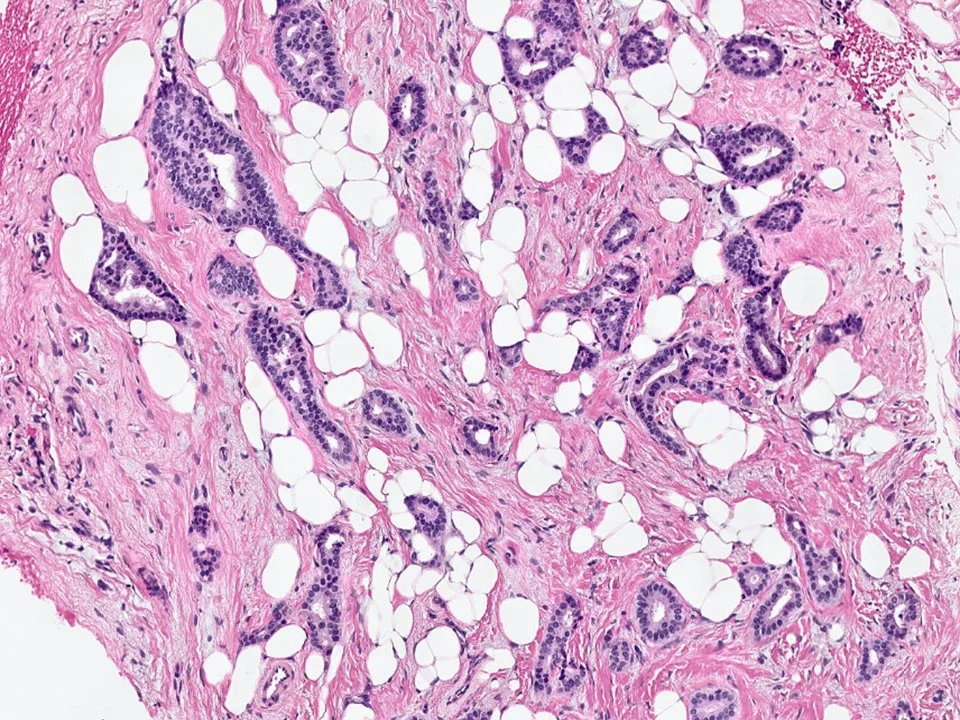

Normal Breast Tissue

Mammary ducts and lobules are embedded in a stroma that is composed of a variable amount of fibrous tissue and adipose tissue. The proportion of fibrous tissue to adipose tissue varies with age and varies amongst individuals. Younger women tend to have denser breast tissue, while older women tend to have fattier breast tissue.